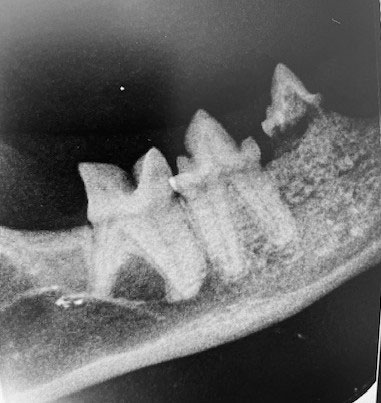

Dentalröntgen – der Goldstandard

• Digitale Zahnradiografie aller Zähne

• Beurteilung von Wurzelresorption, FORL, Abszessen und Frakturen

• Diagnose auch bei äußerlich unauffälligen Zähnen